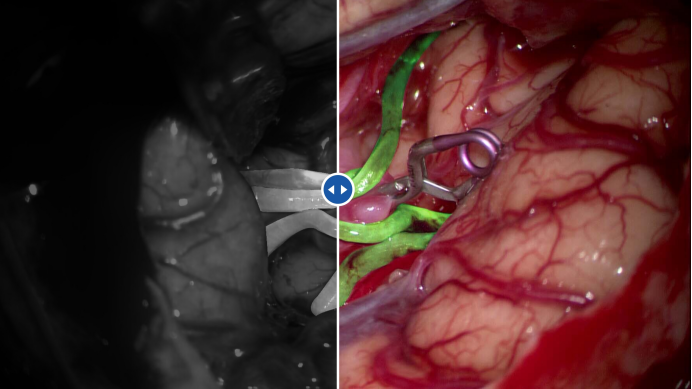

3D增强荧光技术,全面的荧光造影解决方案

图片

作为显微术野的视觉延伸,ES-100提供了包含F460黄荧光、V400 5-ALA荧光*、i800 ICG荧光以及3D增强ICG等多种荧光造影模块,可辅助外科医师观察到细小血管中血流变化以及更准确地判断肿瘤边界,有效增强外科医师的手术信心,进一步提升手术效率和质量。